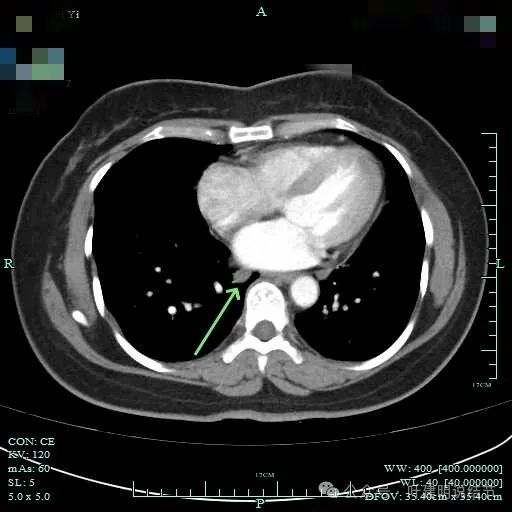

隆突下明显肿大淋巴结

下肺静脉旁肿大淋巴结。

肺门部明显肿大淋巴结。